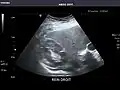

Left kidney -

Kidneys: Right and left kidneys measure 11.5 cm and 12 cm in length respectively. No hydronephrosis. Small left lower pole kidney cyst.